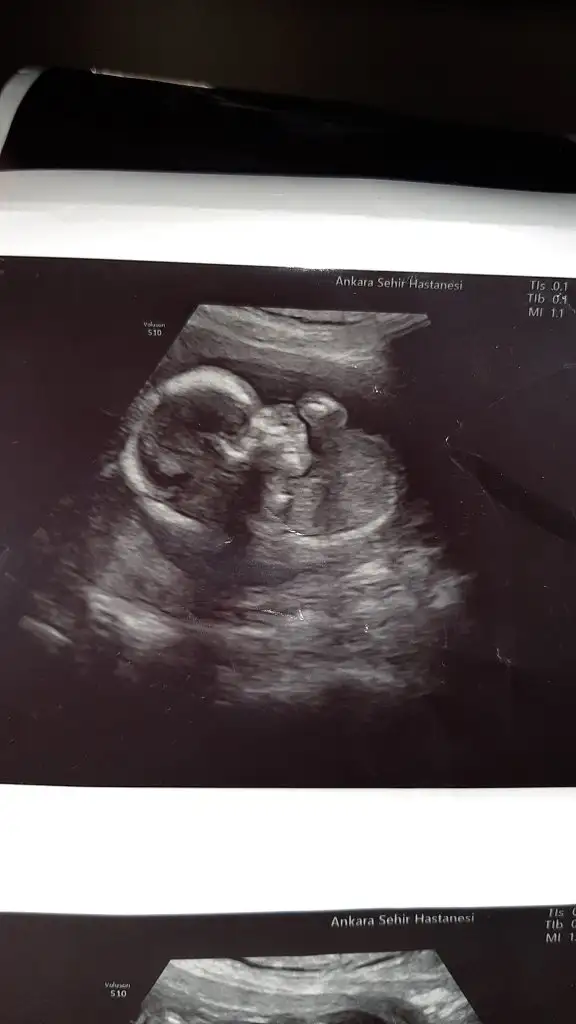

Bugun cinsiyetimizi öğrendik kizim geliyormus hayirlisiyla bakalim

Sağlıkla gelsinBugun cinsiyetimizi öğrendik kizim geliyormus hayirlisiyla bakalim